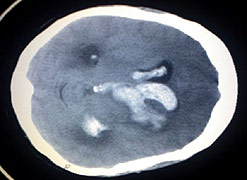

Strokes are caused either by a blockage, when a clot blocks an artery that carries blood to the brain, or when a blood vessel bursts causing a bleed into the brain.

Tests including scans should be carried out quickly to assess the cause of the stroke. Blood-thinning drugs may be given where a clot is involved.